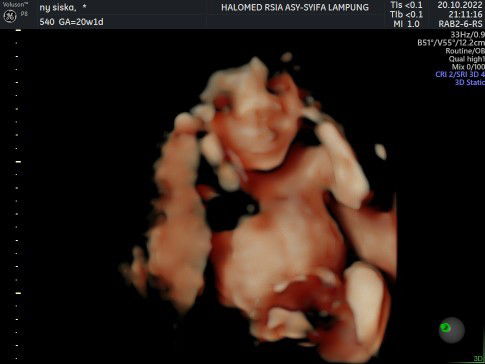

MasyaAllah TabarakAllah Hasil usg hari ini usia kandungan #10w3d after pendarahan di hari sabtu kemarin.. Alhamdulillah pendarahan tinggal sedikit masih disuruh bedrest sampai 2 hari sekian.. Gemes banget joget2 waktu di usg, btw usia kehamilan di usg 11w1d normal kah bunda bunda? Mohon doanya ya semoga kehamilanku sehat hingga lahiran❤❤ masyaAllah masyaAllah ada di resepkan rhinos karnaku lagi pilek